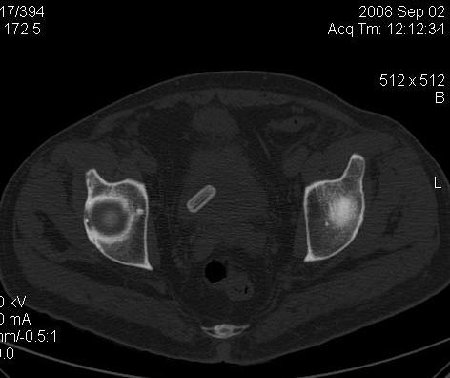

КТ Малого таза.

Что в мочевом пузыре? :?: ;)

Bladder foreign body0003.jpg

Я тоже так думал! Урологи выполнили цистоскопию, оказалось камень, такой причудливой формы.